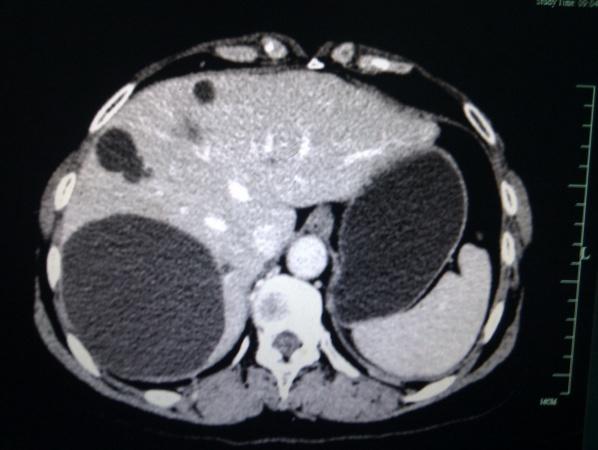

左肾包膜下血肿

自发性双肾包膜下血肿求原因

自发性双肾包膜下血肿,求原因